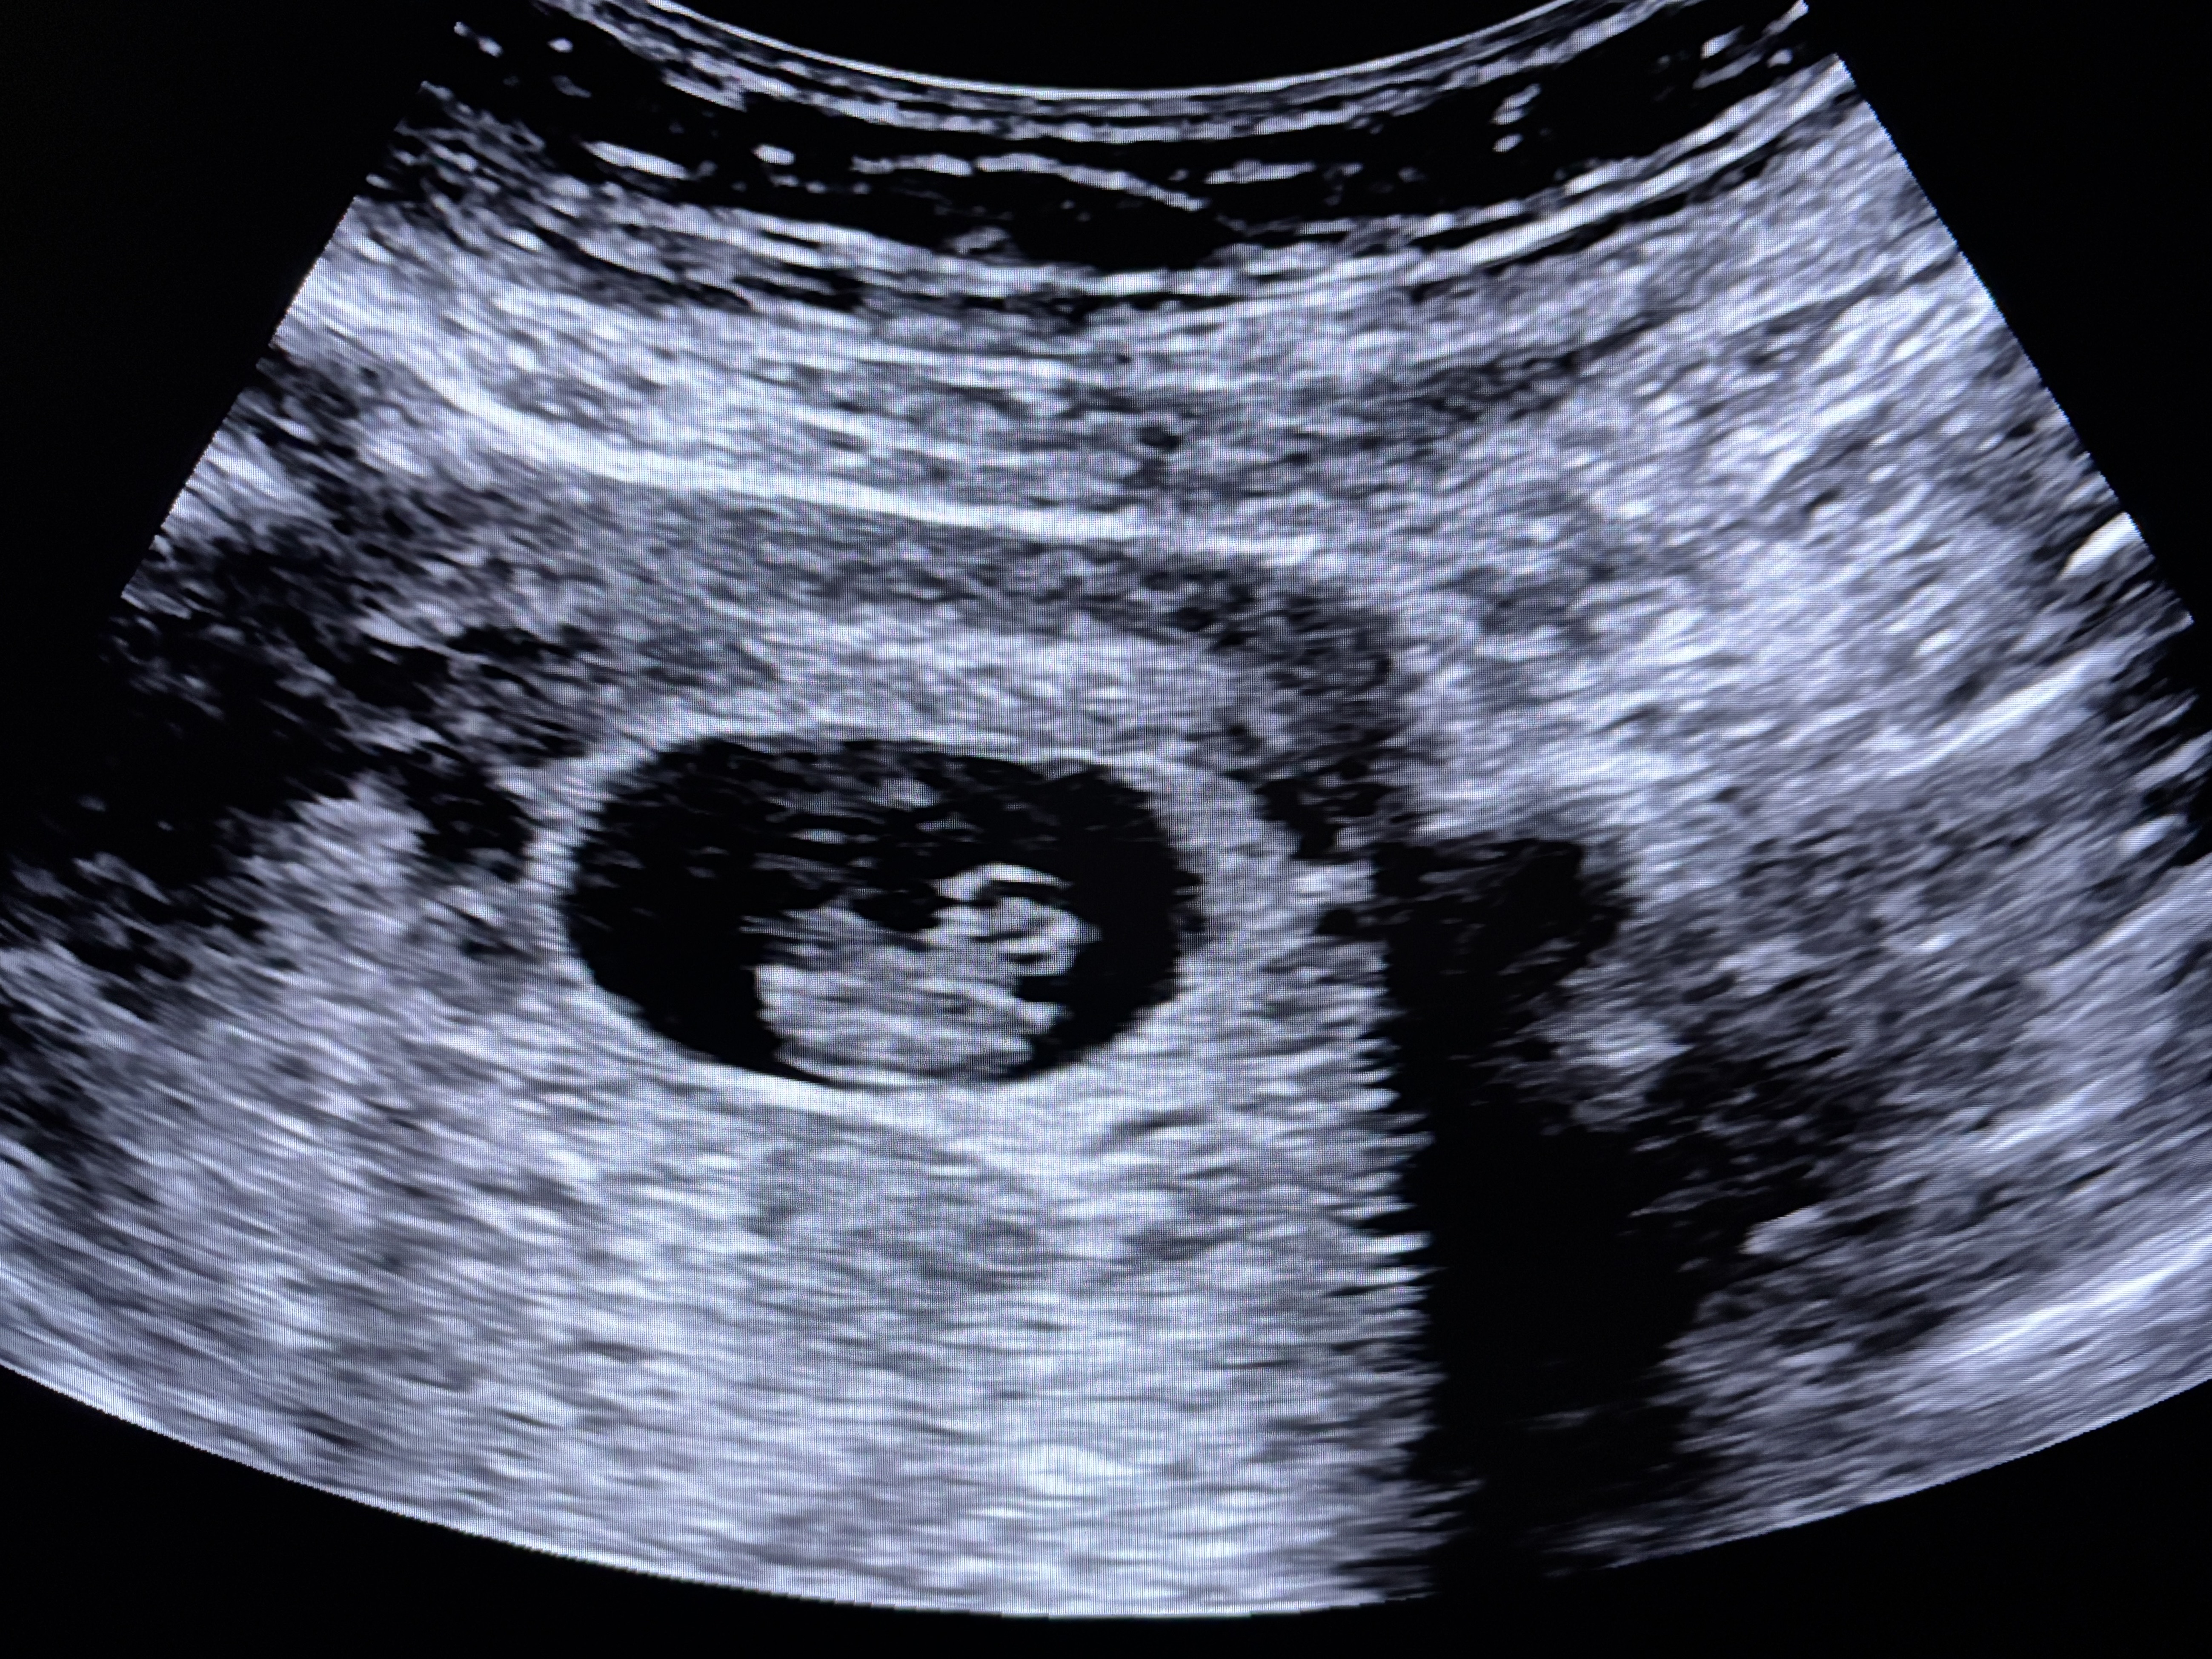

8주차 첫 초음파 보고왔어요~

오늘 아기 처음으로 확인하고 심장소리 듣고왔어요!! 젤리곰을 살짝 기대했으나 옆모습만 보여줘서 카라멜콘..같은ㅋㅋㅋㅋ 근데 또 어떻게보면 귀여운 뚱뚱하트같기도 하구요?!☺️ 외국이다 보니 사진도 영상도 받을 수 없어서 핸드폰으로 찍은 사진만 남았습니다😂 근데 제 배에 저 검은부분들이 뭘까 너무 궁금하네요.. 초음파기사님은 원래 코멘트하지않게 되어있어서 (결과 닥터에게 보내면 닥터가 설명) 그냥 아기 잘 있는거만 확인하고 왔어요ㅎㅎ 캐나다 맘님들 계시면 사설초음파 다들 보셨는지 추천하시는지 어떤지 궁금해요~